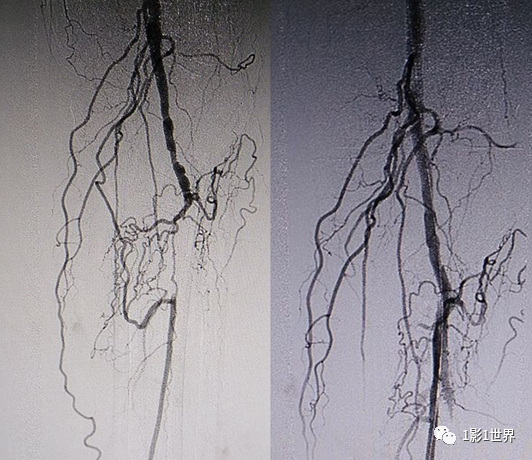

糖尿病20年,左下肢疼痛、间歇性跛行5年,静息痛1年,加重并变黑2个月。住院后下肢CTA示左下肢血管广泛不光滑,节段性轻度狭窄,其中最严重的是左侧股浅动脉中段重度狭窄(约90%),长度约8cm。

介入科DSA血管造影,确认了CTA诊断,同时行球囊扩张,支架置入术,再次造影,股动脉再通,远端血流较好。

什么是外周支架话说介入 | 外周血管狭窄,支架植入术_https://www.jmylbn.com_新闻资讯_第8张术后病人症状缓解,半年后复查血管通畅。